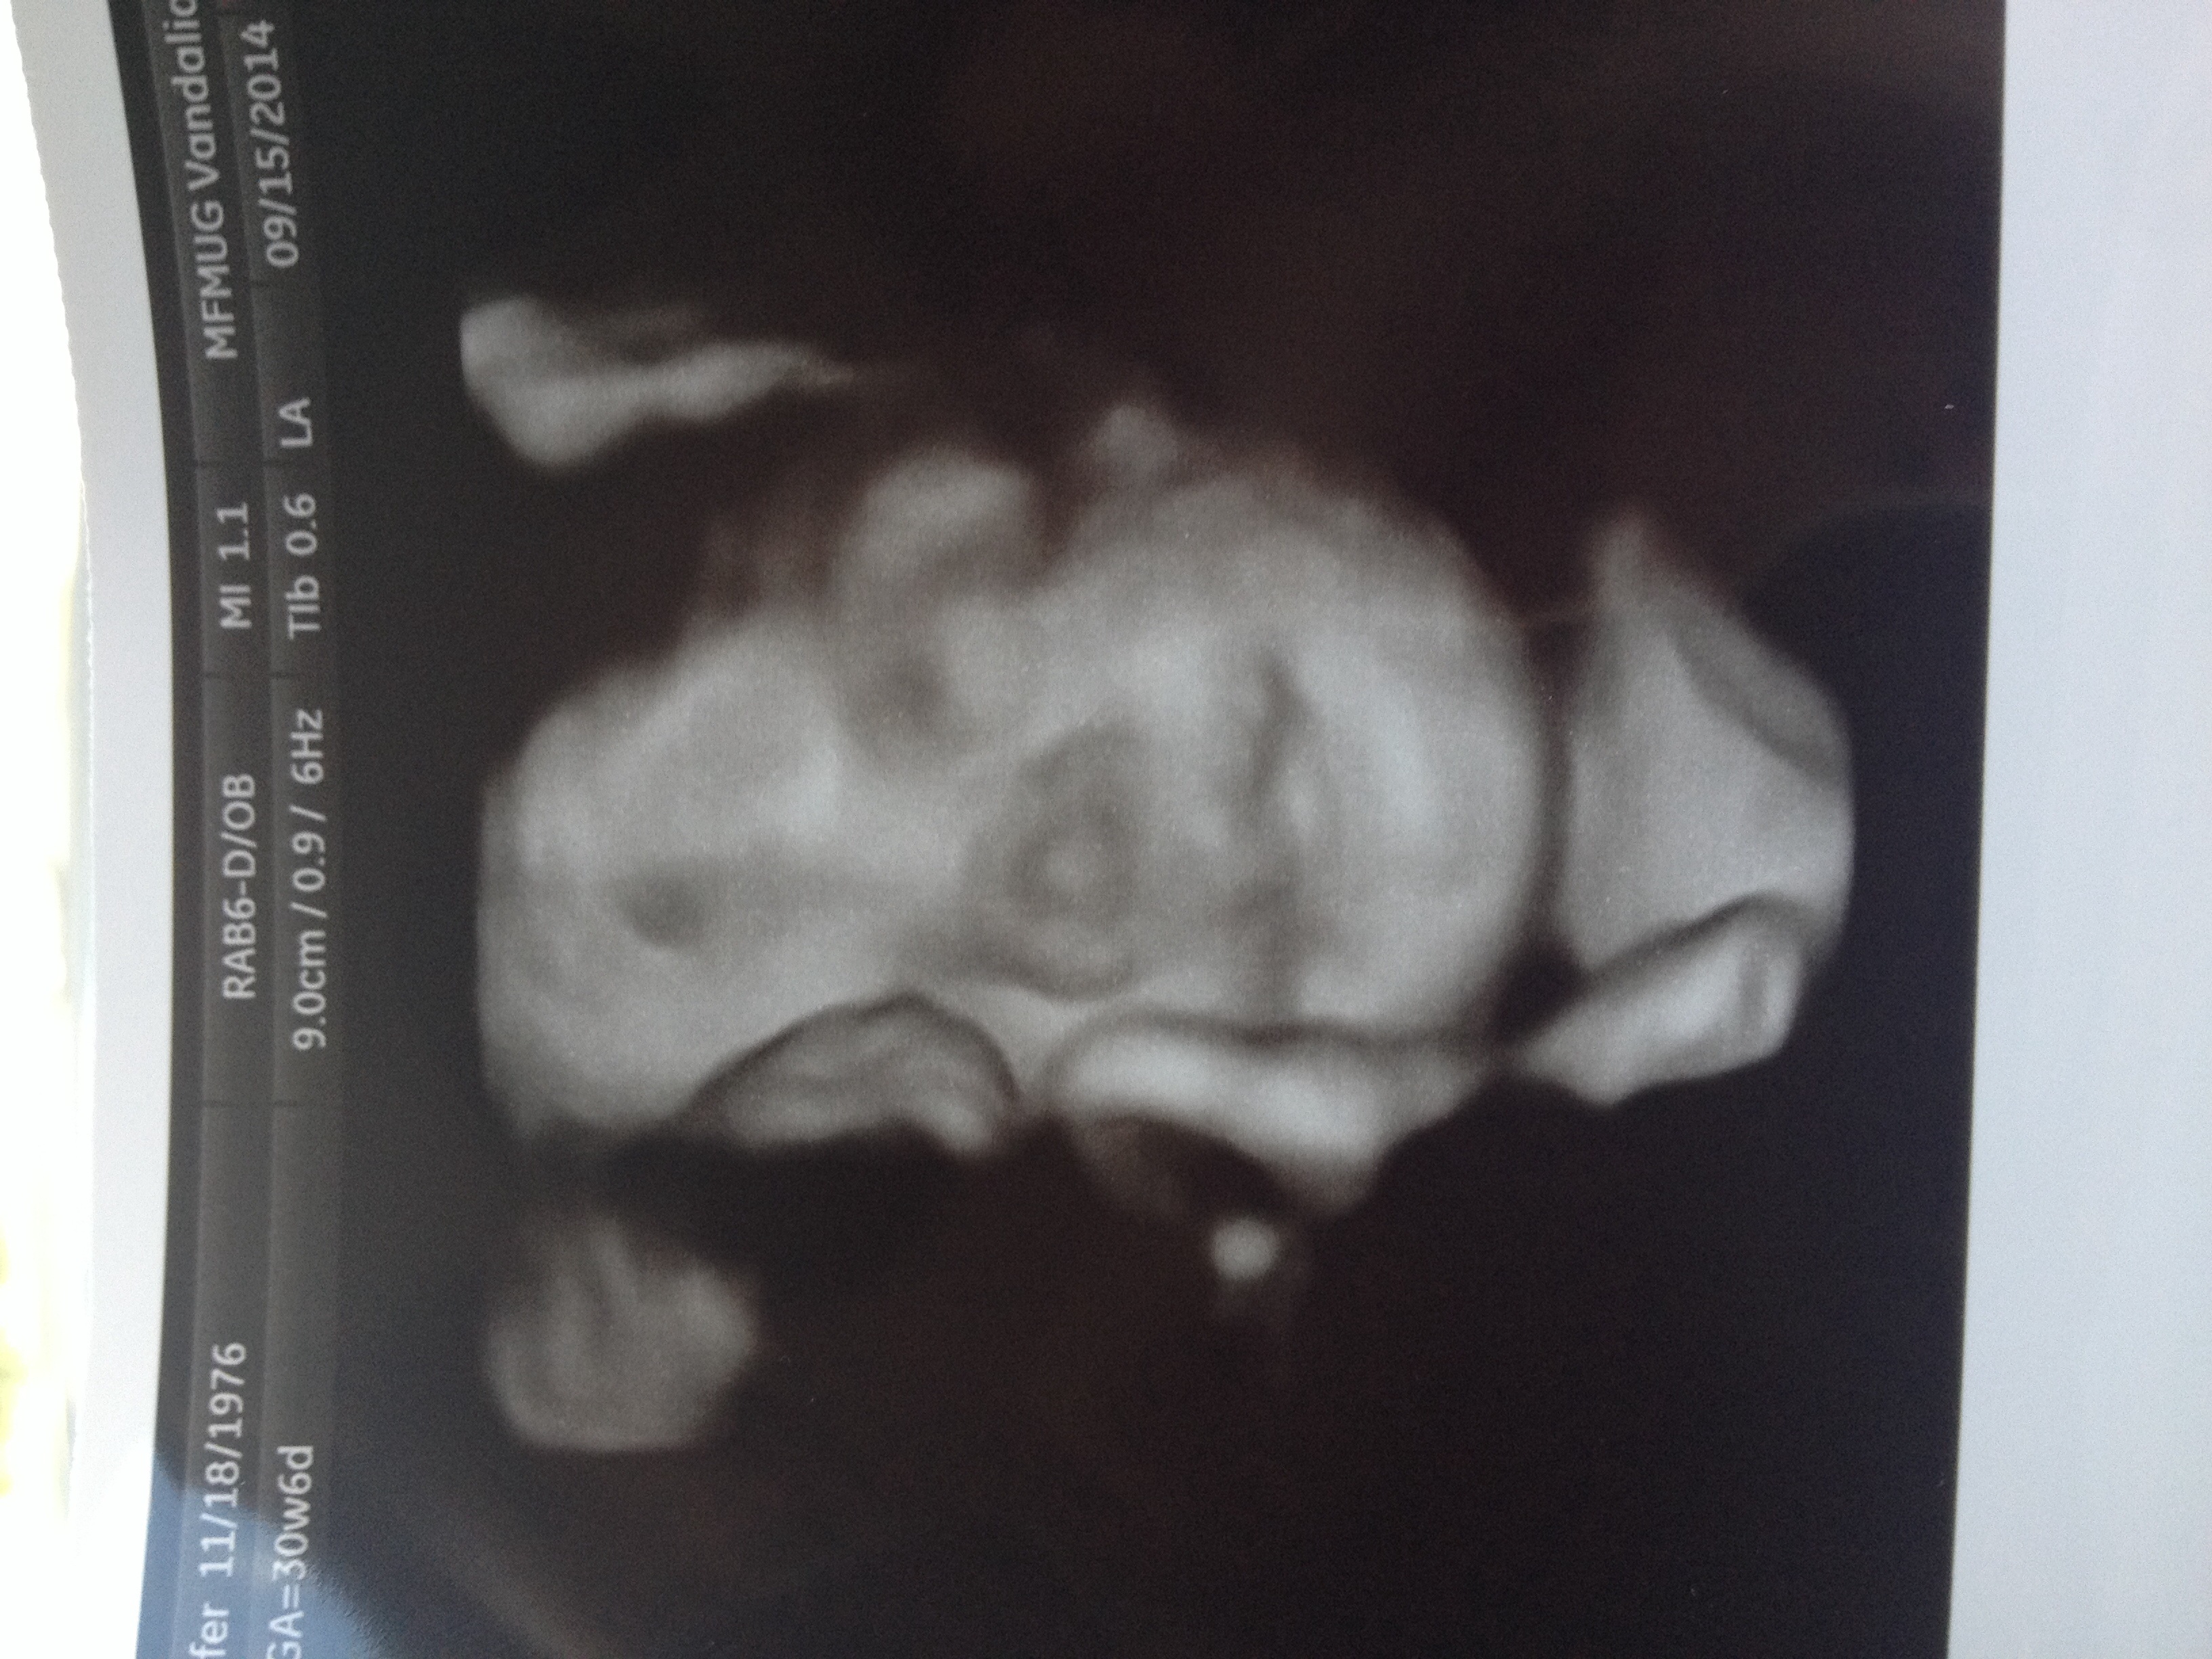

I asked if my high risk office had 3d and they said no they didn't do that but the tech was nice enough to do one but it was hard since her hands and a foot were in her face.